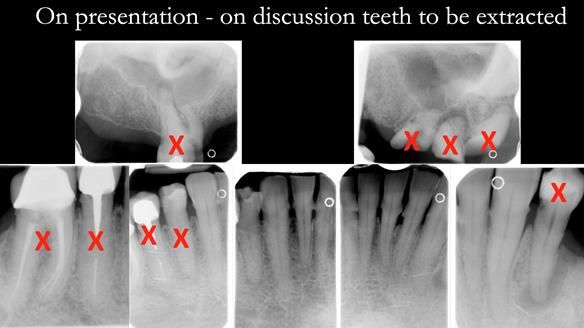

- The upper natural teeth have hopeless prognosis due to dental caries.

- The LR6, 5, 4 have guarded prognosis because of dental caries.

- The lower front teeth (LR3 – LL3) have better prognosis (although, I think there is high chance of loss – over the next 10 - 15 years). However, I do not believe it is right to remove them as they are in good condition compared with the other teeth and coping with a lower full denture is far more difficult (affecting your quality of life) than a lower metal based partial denture supported by natural teeth as proposed in the treatment plan below.